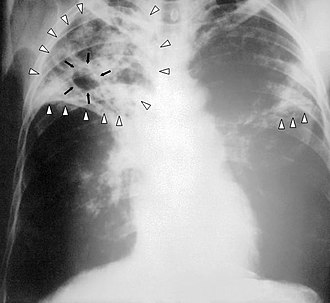

Туберкулезна бактерия способна поражать почти все ткани человеческого тела – от кожи до костей. Но свыше 80% случаев – это туберкулез органов дыхания, знаменитая чахотка.

К методам профилактики туберкулеза относятся противотуберкулезные прививки вакциной БЦЖ и БЦЖ – М. Прививку детям делают в родильном доме на 3 – 7 день жизни. Дети с длительными медицинскими отводами прививаются в условиях детской консультации. Так же детям из групп социального риска ставится проба Манту или Диаскин – тест. Подросткам с 16 лет и взрослым проводится флюорографическое обследование органов грудной клетки, позволяющее выявить ранние формы туберкулеза, когда лечение наиболее эффективно.

К первым признакам туберкулеза относятся быстрая утомляемость, общая слабость, снижение или отсутствие аппетита, потеря веса, повышенная потливость по ночам, незначительное повышение температуры тела (37.2 – 37.5), одышка, кашель с мокротой, кровохарканье.